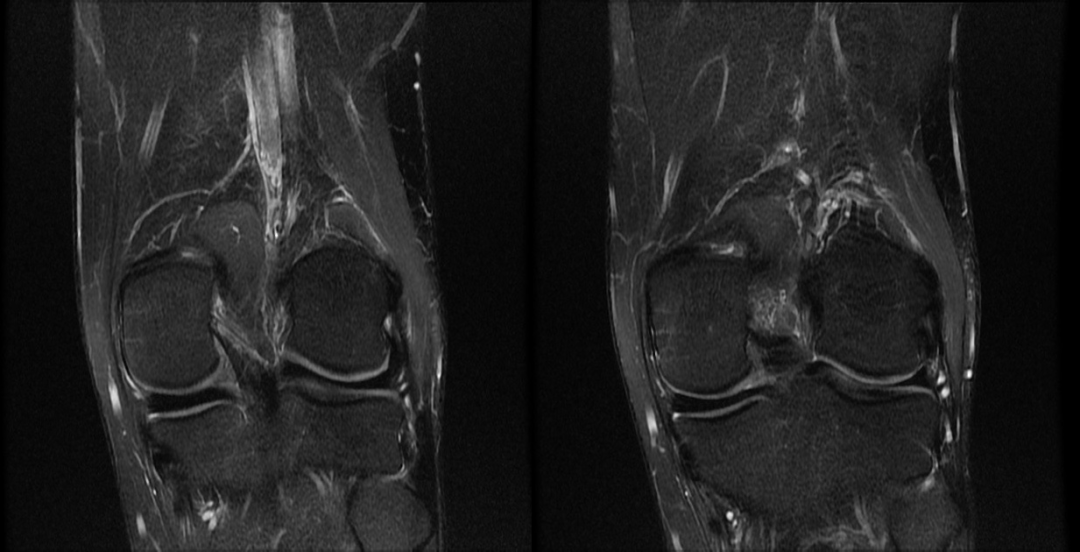

主诉:右膝关节外侧反复疼痛不适半年余,近一个星期疼痛加重。现病史:患者右膝关节外侧间歇性疼痛不适半年余,近一个星期疼痛加重,屈膝时明显,门诊行膝关节 X 线片检查,未见明显异常。患者否认手术史/外伤史。为进一步明确情况,我们建议患者行膝关节磁共振检查;图像如下:T1

T2 压脂

冠状位

大家是否发现什么异常?该患者是膝外侧疼痛不适的症状,我们重点观察了外侧半月板及外侧副韧带,但是我们发现是正常的;

但是我们发现有一个地方信号不对;

大家发现了没有?那这是什么呢?

那么我们刚刚看到信号增高的就是髂胫束,排除了半月板和外侧副韧带的问题,那么膝关节外侧疼痛是不是这个原因导致的呢?

1 T2WI PD 序列上可以显示靠近股骨外侧髁与髂胫束之间的信号增高,边界不清,外侧滑膜增厚;

2 髂胫束靠近股骨外侧髁水平出现增厚改变,部分严重患者可以出现连续性中断;3 髂胫束表面或深部信号明显增高;4 可伴股骨外侧髁反应性骨髓水肿